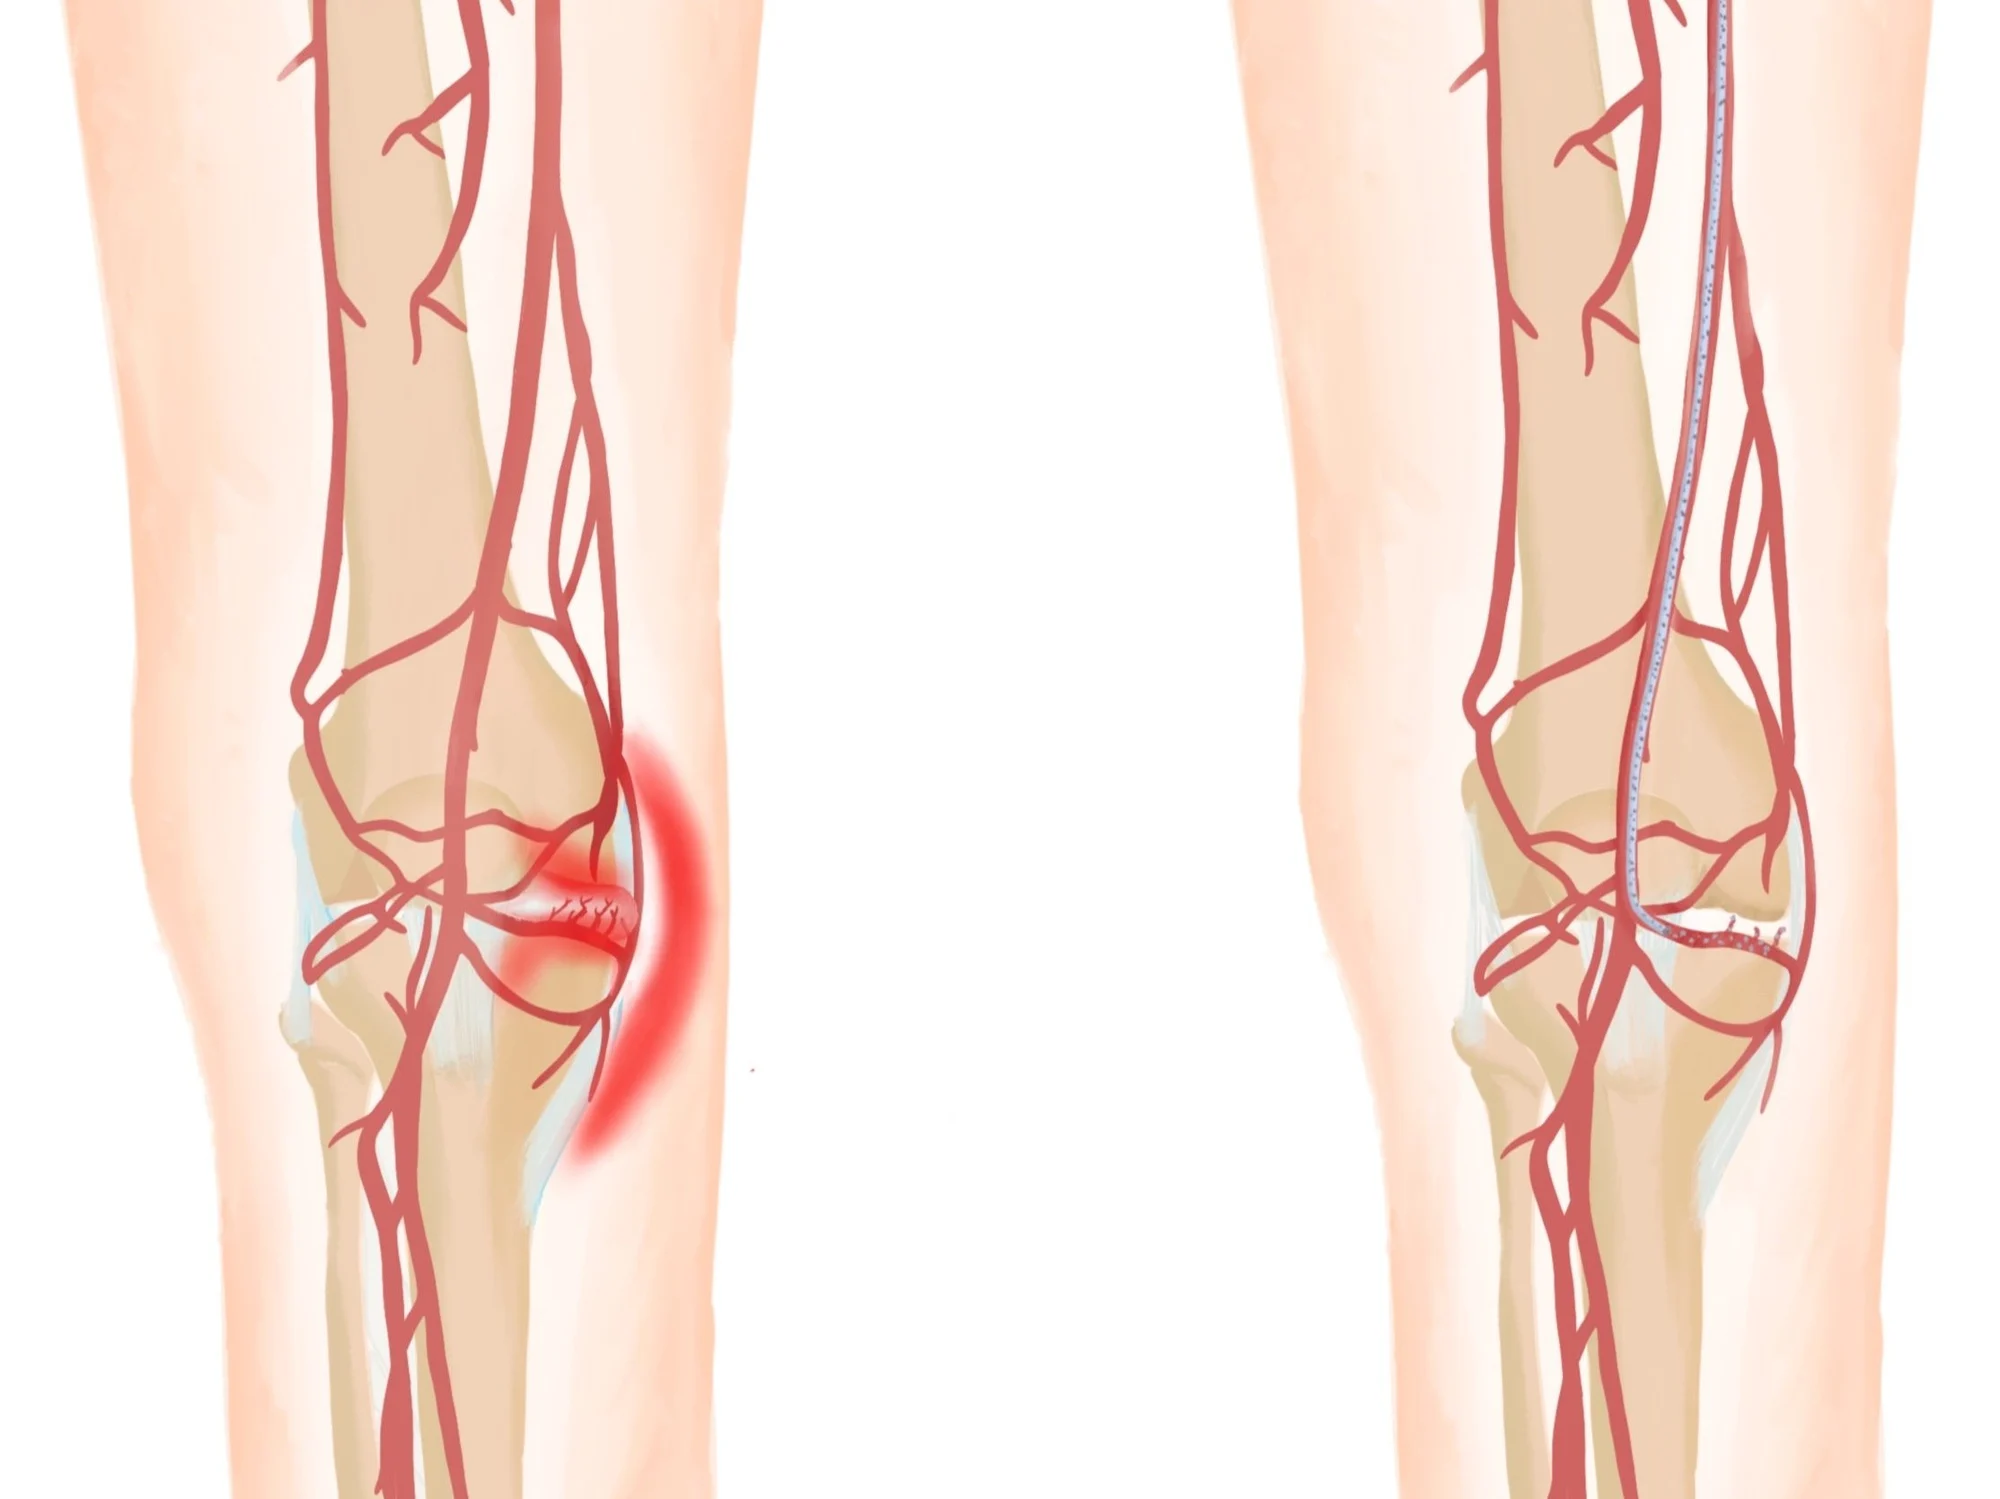

Genicular Artery Embolization

Thanks to remarkable advances in imaging and device technology, we can now reach diseased areas in the body through a tiny needle puncture, and deliver highly targeted treatments with precision, while preserving surrounding healthy tissues. This means less pain, faster recovery, and fewer complications compared to conventional surgery.

After completing my medical training, residency and advanced fellowship in Vascular & Interventional Radiology from the best institutes in the country, I’ve dedicated my career to offering precise, minimally invasive treatments for wide variety of complex conditions like uterine fibroids, thyroid nodules, varicose veins, prostate enlargement, knee joint pains, liver diseases, cancer and many more. Although technology enables precision in Interventional Radiology, but it is compassion, empathy, and ethics that bring meaning to medicine and guide every decision I make in my patient treatment.